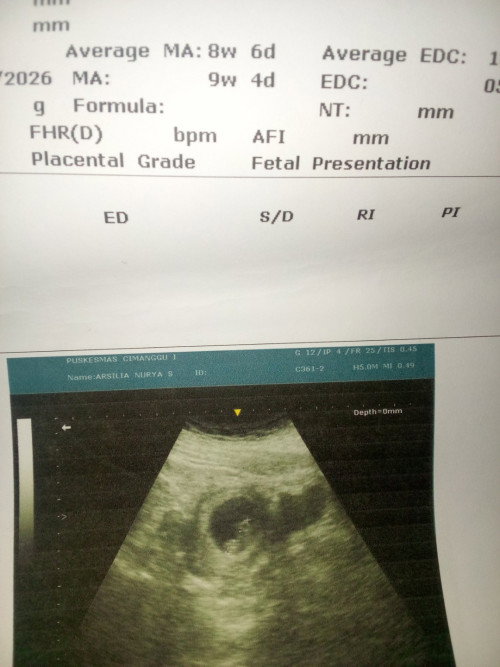

Maaf bund barangkali disini ada yg punya pengalaman ngflek atw kluar bercak tapi ga tiap hari jdi misal dalam waktu seminggu cuma 3harinya yg ngflek tapi dalam jumlah sdkit hanya bercak kadang warna merah mudah kadang coklat? Barang x ada yg pernah ngalamin? Soalnya saya juga punya riwayat hamil 2X itu ngflek smua... Hamil pertma ngflek bahkan bukan flek lgi udah kyak mens aja darahnya cuma janinnya bagus djj bagus dll jdinya d pertahanin pake penguat alhamdulillah berhenti dlm waktu sminggu... Hamil kedua ngflek juga awalnya tapi lama lama bnyak cuma itu ga bisa trslamatkan karena janinnya berhenti berkembang d 7week dan itu d kuret.. Nah cuma x ini beda ya itu flek cuma bercak sdkit dan itu ga tiap hari jdi kadang kadang aja knpa yaa ada pernah ngalamin??? #mohonbantujawabbunda #Sharingdong_Bund #bantujawab #sharing